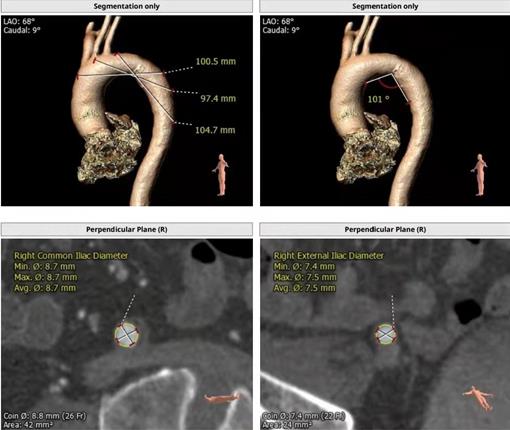

术前CTA评估

患者年龄大,合并疾病较多,心血管病医院吴栋梁院长及CCU病区李新国主任向院领导汇报。姚晓峰党委书记、张海涛院长高度重视,由医务部牵头,协调组织心内科介入团队、CCU、导管室、心外科、影像科、超声科、麻醉科、外科手术室进行了MDT术前讨论会。经讨论一致认为采取外科常规体外循环下开胸主动脉瓣膜置换术存在较大的风险,术后发生切口愈合不良、多器官功能衰竭可能性极高。依据指南建议,有行经导管主动脉瓣植入术(TAVR)指征,并缜密制定手术方案及相关预案。经与家属充分沟通后,家属同意手术。

经过前期充分准备,于2月20日上午为患者实施TAVR手术。手术历时2小时,术中精准穿刺、导丝顺利跨瓣、球囊预扩充分、输送器顺利过弓、瓣膜精准零位释放等操作一气呵成。造影及食道超声评估瓣膜位置、形态良好,左心室与主动脉根部压力阶差由术前75mmHg,降至术后10mmHg。手术顺利,术后半小时患者苏醒、1小时拔除气管插管,患者生命体征稳定。